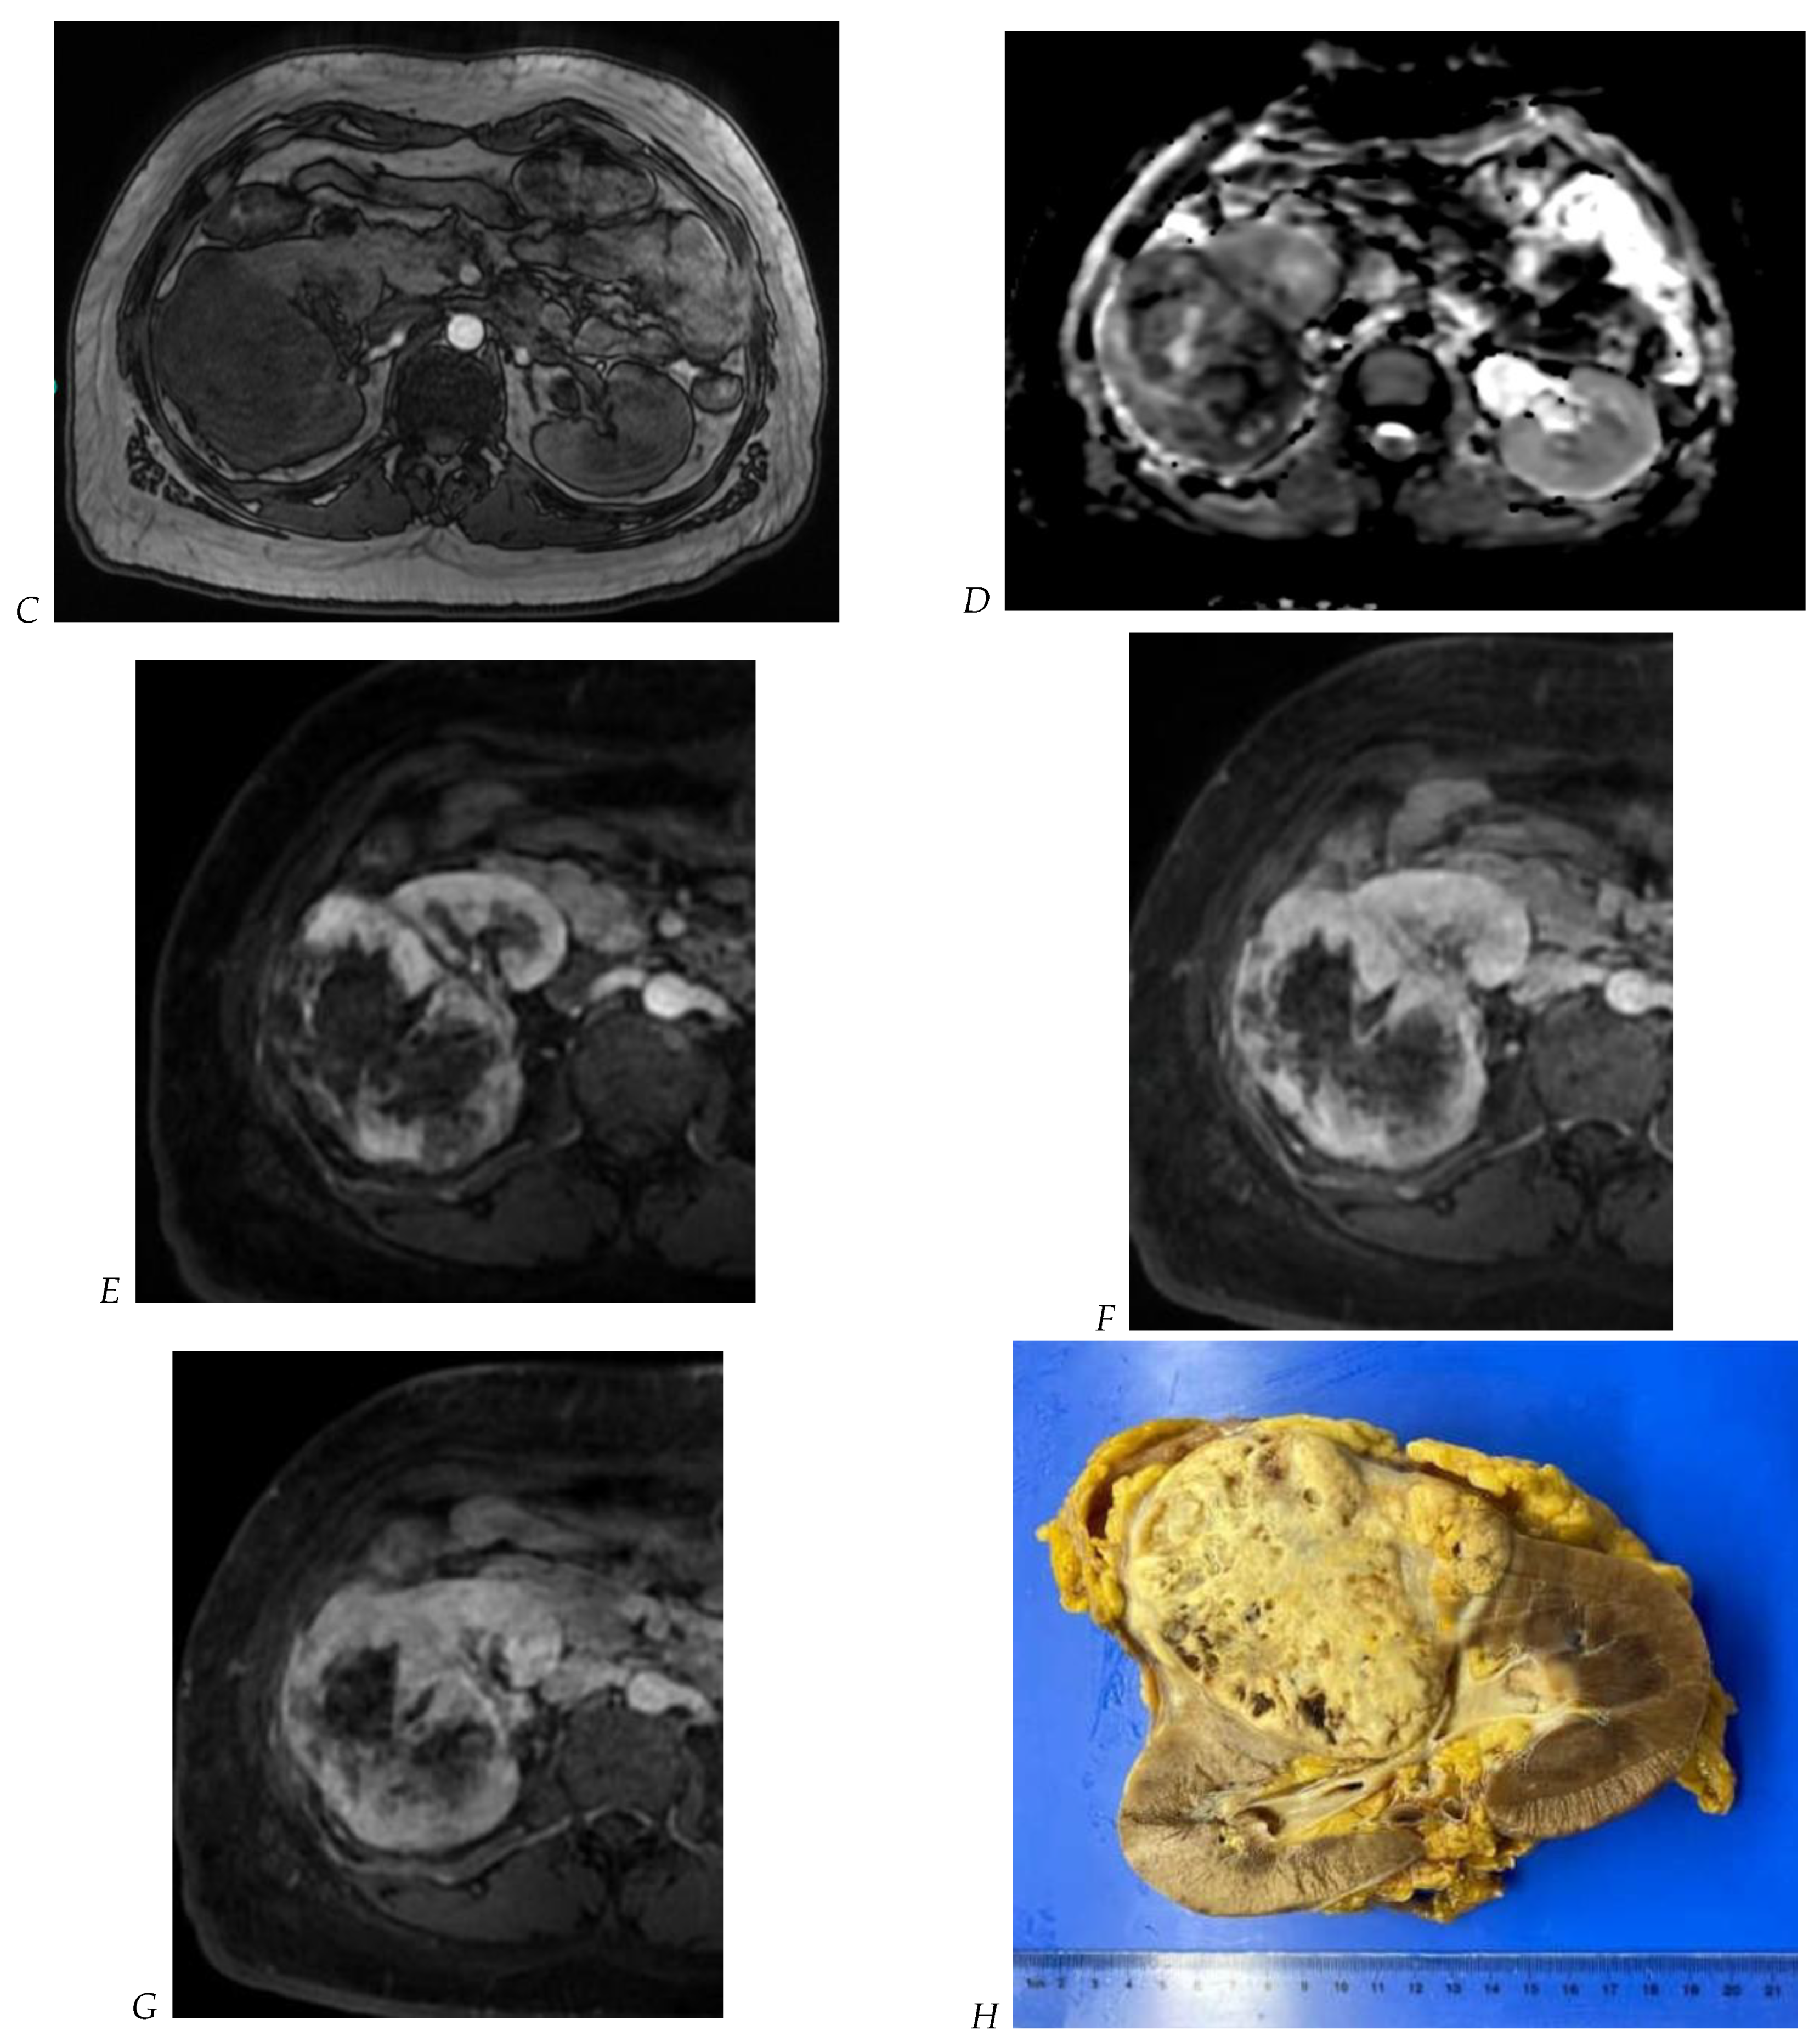

Figure 5.

Clear cell renal cell carcinoma in the right kidney of a 52-year-old-man. (A) Coronal T2-weighted fast SE image shows a large heterogeneous mass with areas of high signal intensity compared with renal parenchyma. Transverse in-phase (B,C) opposed-phase MR images show a subtle signal loss on the opposed-phase image. (D) The ADC map is heterogeneous with predominant areas of restriction of tumor diffusion. Transverse gadolinium-enhanced T1-weighted gradient-echo spoiled MR images in (E) corticomedullary, (F) nephrographic, (G) and delayed phase images show intense and rapid peripheral enhancement during the arterial and nephrographic phases followed by a rapid washout of contrast on the delayed phase. Central necrotic areas do not enhance. (H) Macroscopic view of the lesion after radical nephrectomy. The lesion appears heterogeneous. Courtesy of Pr S. Ferlicot, Department of Pathology, Bicêtre Hospital.